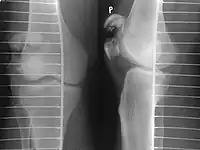

Some people have a normal bipartite patella or two-part patella which can appear as a fracture. The fragment is usually seen in the top outer corner of the patella and can be distinguished from a fracture by being present in both knees.[6]